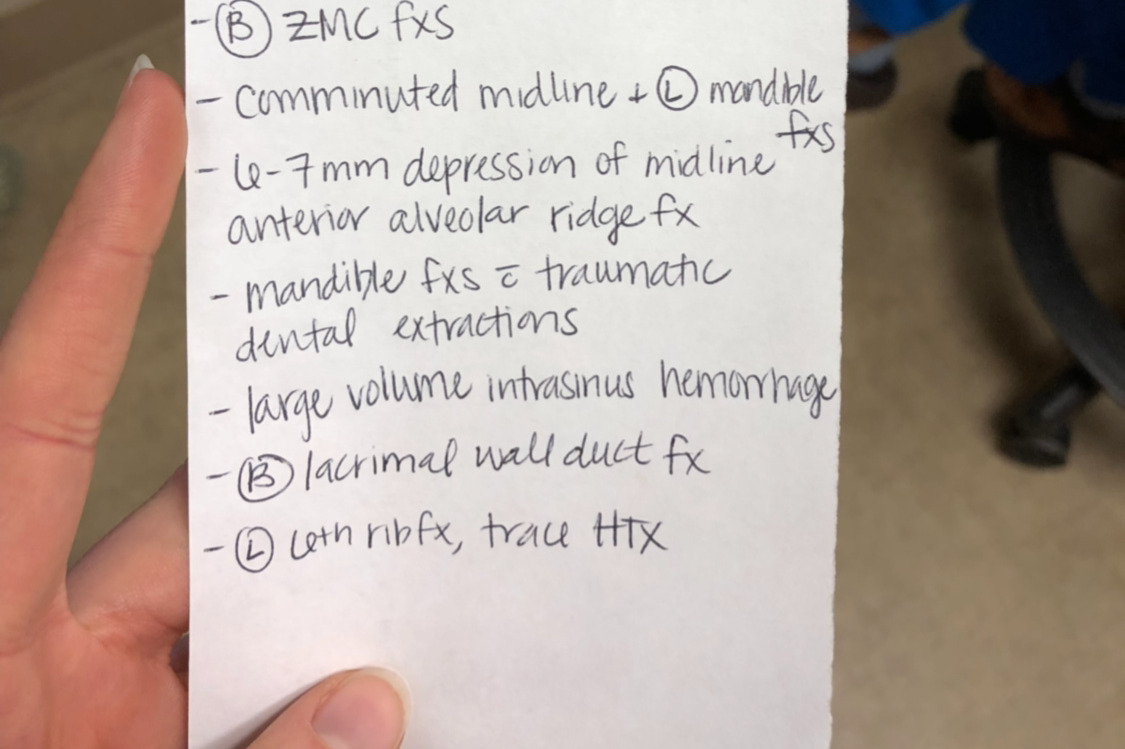

That evening, he went back for a 6-7 hour surgery. Here is a list that one of the nurses gave me that lists all of the bones that were broken. Little did we know, but this was just the beginning. Currently, he is still awaiting a bone grant surgery and dental implants. Ruled as cosmetic and a surgery that will NOT be covered by insurance. It comes to a total of approximately $32,000 for the upcoming surgery alone.

Due to his injuries, he also had a feeding tube and a tracheostomy. Once off of both of these, he was on a strict diet of pureed foods. It was difficult for him to build his strength up when his diet was so limited. With the combination of injuries, he was out of work for about two months, which does not help when the medical bills are piling up.

That evening, he went back for a 6-7 hour surgery. Here is a list that one of the nurses gave me that lists all of the bones that were broken. Little did we know, but this was just the beginning. Currently, he is still awaiting a bone grant surgery and dental implants. Ruled as cosmetic and a surgery that will NOT be covered by insurance. It comes to a total of approximately $32,000 for the upcoming surgery alone.

Due to his injuries, he also had a feeding tube and a tracheostomy. Once off of both of these, he was on a strict diet of pureed foods. It was difficult for him to build his strength up when his diet was so limited. With the combination of injuries, he was out of work for about two months, which does not help when the medical bills are piling up.